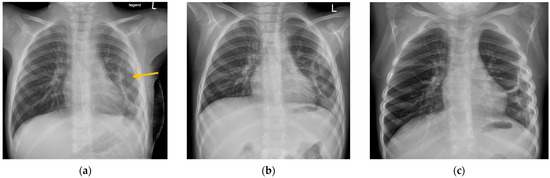

During our inpatient treatment, a pneumothorax was detected in 20 out of 47 patients (43%). Pneumothorax was still detectable in 11 patients at the time of their discharge from inpatient treatment. At the end of our FU, a spontaneous resorption of the pneumothorax was observed in eight patients (Figure 2). In three patients, a pneumothorax ex vacuo remained identifiable. The course of treatment is shown below (Figure 3).

Figure 3. Treatment process of the study population.